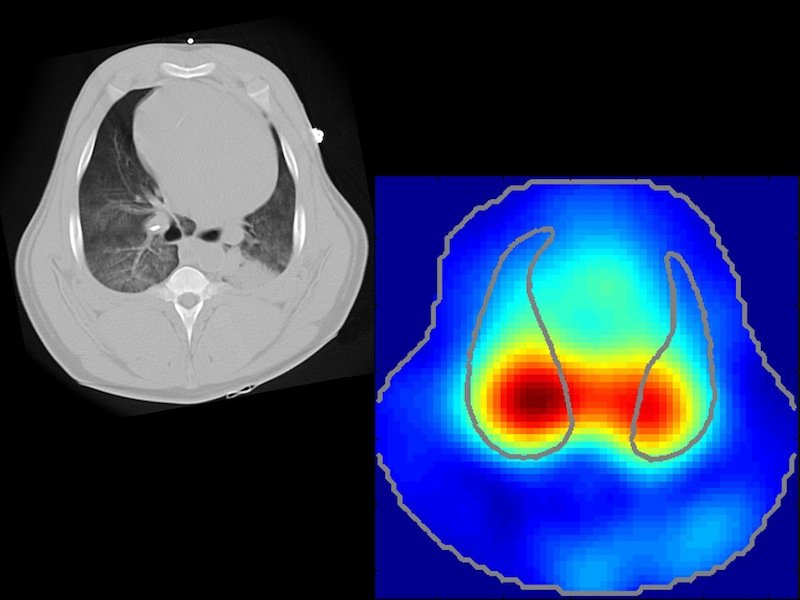

Bei dem neuen Verfahren werden Computertomographie und Bioimpedanzdaten zusammengeführt.

Quelle: TU Wien

„Mit Computertomographie kann man räumlich hochauflösende Bilder erzeugen. Doch den zeitlichen Verlauf der Lungenfunktion kann man damit nicht kontinuierlich beobachten“, sagt Professor Eugenijus Kaniusas vom Institut für Electrodynamics, Microwave and Circuit Engineering der Technischen Universität Wien.

Beim Einsatz des Lungengürtels mit 32 Elektroden werde weder die genaue Form des Brustkorbes noch die individuelle Lage der Organe berücksichtigt, so die Wiener Wissenschaftler. Mit der neuen Kombitechnik ließe sich sowohl zeitlich als auch räumlich eine sehr hohe funktionelle Auflösung zur Überwachung der Lungenfunktion erreichen. Den Elektrodengurt stellt das Schweizer Start-up Swisstom aus Landquartin im Kanton Graubünden her.